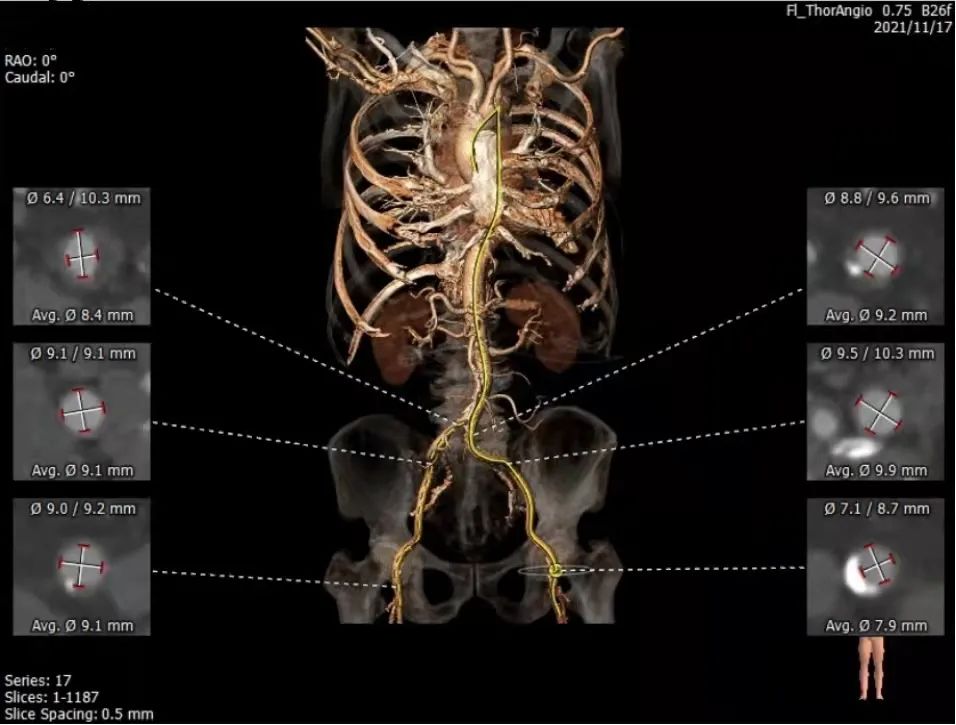

主动脉瓣CT评估

三叶瓣,瓣环径24mm,瓣环长短径分别为27.3*20.4mm,周长为75.5mm,面积为436.8mm²。左室流出道25.7mm,法式窦27.2mm*30.6mm*30.6mm,左冠高度19.3mm,右冠高度16.7mm,窦管交界 25.9mm,升主动脉直径29mm。

血管入路评估

综合评估

钙化位置高,冠脉高度可,双下肢内径可,术者决定采用22mm球囊预扩,选择植入25mm silara瓣膜。